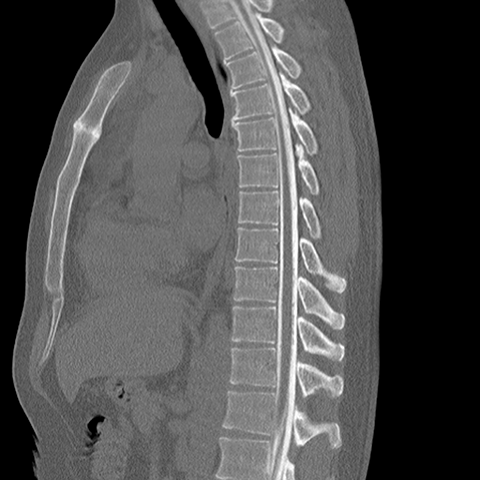

Sagittal CT Myelogram, thoracic spine [3 of 3]